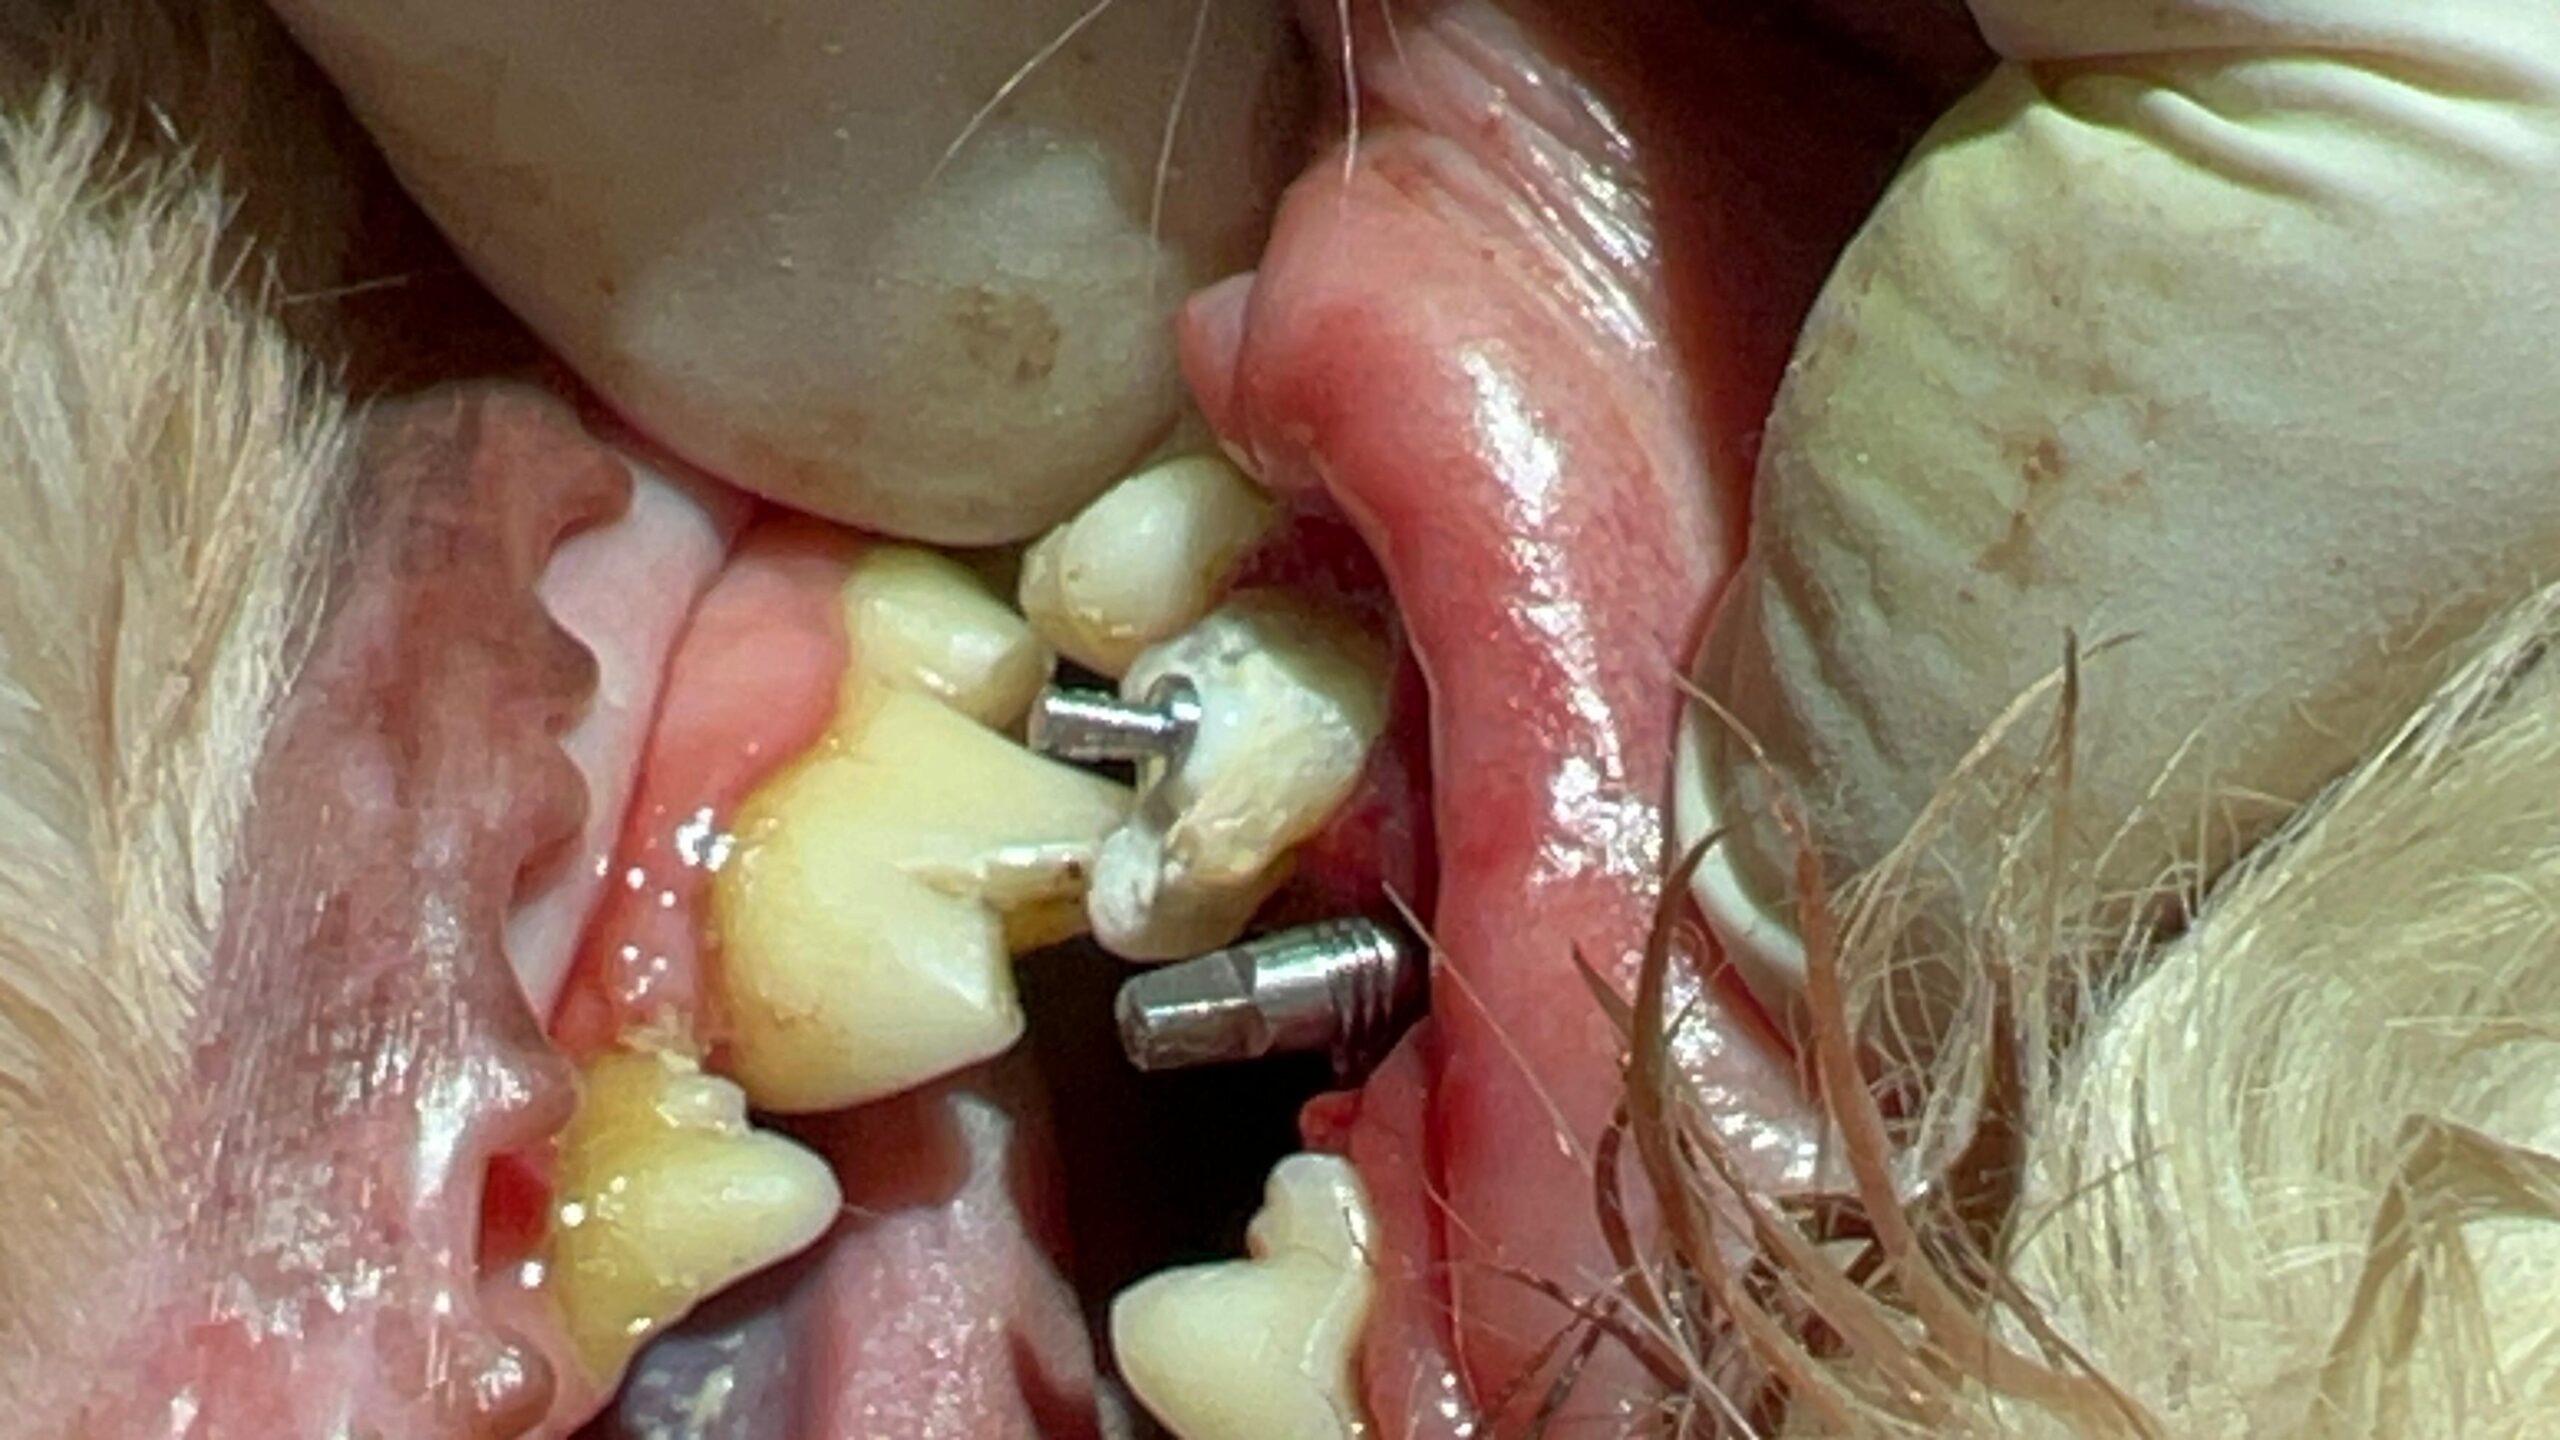

Implantología, planificación y colocación de implantes dentales en el hueso maxilar o mandibular para sustituir piezas dentales perdidas o ausentes. Utilizamos tecnología avanzada para diseñar y rehabilitar sobre ellos la prótesis, garantizando un ajuste y resultado perfecto..

Implantología Dental

Nuestro equipo veterinario especializado combina conocimiento clinico, ingeniería digital y bioseguridad avanzada para ofrecer una experiencia integral. Cada procedimiento se realiza bajo los mas altos estándares de calidad, priorizando el confort, la seguridad y la comodidad de tu compañer@.